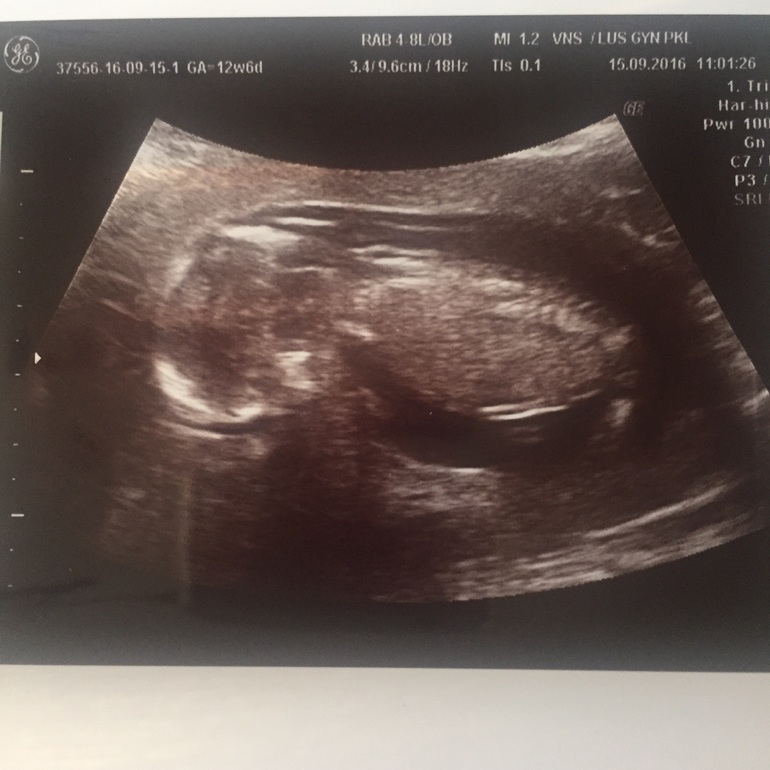

УЗИ 15.9

вот мы и сходили здесь на УЗИ ,или у меня как всегда все через одно место или удись-ка "профи" попалась... Мерила -мерила никак ей все было не померять:( срок по мес 12+6 был , она намерила и 14+2 и 13+6 в итоге на этом остановились, ворот . Пространство 2,2 намерила кровь еще не пришла:( хорошо я в Питере уже сходила, а то с ума сошла бы :( пол сказала непонятно пока , на след УЗИ посмотрим ( 2.11) :) я уже в Питер доеду:)

На первом скрининге. Не помню , недель в 12.5.